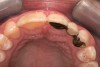

A 9-year-old girl, referred to a prosthodontic office by her pediatric dentist, presented with her mother’s chief complaint: “The kids are teasing her about her big front tooth.” Findings from radiographic and clinical examinations revealed fused maxillary central-peg lateral incisors, teeth Nos. 7 and 8, and a congenitally missing lateral incisor, tooth No. 10 (Figure 1 through Figure 3). An implant was selected as the ideal treatment to replace tooth No. 10 when somatic growth was complete. A diagnostic wax-up was fabricated to determine if the fused tooth could be made to resemble two teeth, using pink composite to give the illusion of an interproximal papilla. The patient was referred for an orthodontic consultation to plan for closure of the diastema between teeth Nos. 8 and 9 and achievement of proper alignment for implant No. 10. The patient was also referred to a periodontist for pretreatment assessment of the tooth No. 10 site. An endodontist was consulted should exposure of the large pulp occur during tooth preparation.

Fig 1 and Fig 2. Pretreatment photographs. Patient at 9 years of age on presentation.